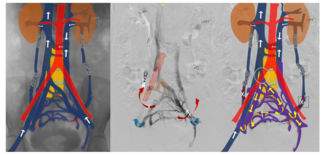

In this case, the symptoms of PCS resulted secondary to venous obstruction. A variant form of May-Thurner syndrome was identified on contrast-enhanced CT, where the common trunk of the IIVs was compressed by the right common iliac artery.